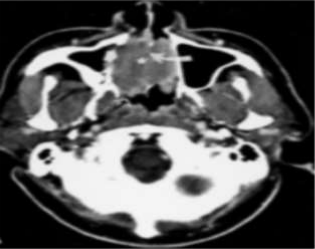

A 38yr old female was reported to the Department of Radiotherapy in the month of July at MNJ Cancer Hospital due to chief complaints of intermitent epistaxis from nose since 3months,In addition,the patient reported difficulty in swallowing ,persistent nasal obstruction and snoring.A phyisical examination revealed a mass seen in nasopharynx.on clinical examination of neck,a node is present on the left side of neck level 2 was seen. Magnetic Resonance Imaging of head and neck showed evidence of Nasopharynx-T1/T2 isointense moderatly homogenously enhancing soft tissue density lesion in nasopharynx along the midline approximately m/s 32x30mm ,superiorly fat planes lost with planum sphenoidale.Inferiorly fatplanes lost with distal aspect of hardpalate.Anteriorly fat planes lost with superior and middle turbinate(Right>left). There is evidence of few enlarged level IB, 2 nodes on the left largest m/s 18x15mm at level 2a.

Figure 1

Figure 2

Figure 3